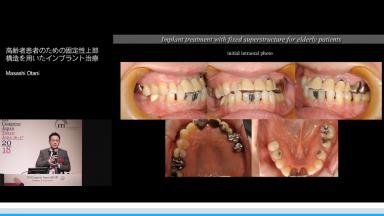

高齢者患者のための固定性上部構造を用いたインプラント治療

咀嚼機能の回復による栄養摂取は,オーラル・フレイル予防の点から重要である.無歯顎の高齢患者に対して,下顎位の設定という観点からインプラント支持型上部構造を提供する際の理論と実際を提供する.